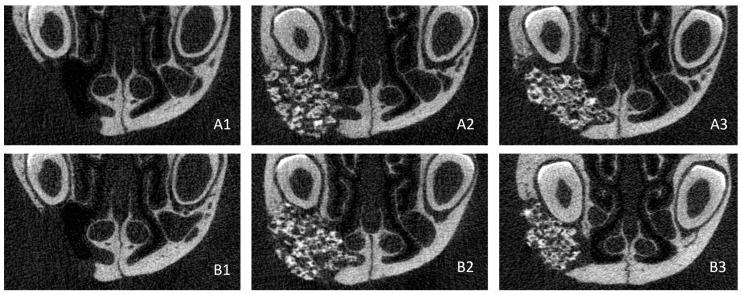

Alveolar cleft is a common congenital deformity that requires surgical intervention, notably using autologous bone grafts in young children. Bone substitutes, in combination with mesenchymal stem cells (MSCs), have shown promise in the repair of these defects. This study aimed to evaluate the regenerative capabilities of a granular bone substitute using an optimized alveolar cleft model. Thirty-six rats underwent a surgical procedure for the creation of a defect filled with a fragment of silicone. After 5 weeks, the silicone was removed and the biomaterial, with or without Wharton's jelly MSCs, was put into the defect, except for the control group. The rats underwent μCT scans immediately and after 4 and 8 weeks. Analyses showed a statistically significant improvement in bone regeneration in the two treatment groups compared with control at weeks 4 and 8, both for bone volume (94.64% ± 10.71% and 91.33% ± 13.30%, vs. 76.09% ± 7.99%) and mineral density (96.13% ± 24.19% and 93.01% ± 27.04%, vs. 51.64% ± 16.51%), but without having fully healed. This study validates our optimized alveolar cleft model in rats, but further work is needed to allow for the use of this granular bone substitute in the treatment of bone defects.

牙槽嵴裂是一种常见的先天性畸形,需要手术干预,尤其是对幼儿使用自体骨移植。骨替代物与间充质干细胞(MSCs)联合使用,在修复这些缺损方面已显示出前景。本研究旨在使用优化的牙槽嵴裂模型评估颗粒状骨替代物的再生能力。36只大鼠接受了手术,制造一个填充有硅酮碎片的缺损。5周后,取出硅酮,除对照组外,将生物材料(含或不含脐带华通氏胶间充质干细胞)放入缺损处。大鼠在即刻、4周和8周后进行μCT扫描。分析显示,在第4周和第8周时,两个治疗组的骨再生与对照组相比有统计学上的显著改善,无论是骨体积(分别为94.64%±10.71%和91.33%±13.30%,对照组为76.09%±7.99%)还是矿物质密度(分别为96.13%±24.19%和93.01%±27.04%,对照组为51.64%±16.51%),但均未完全愈合。本研究验证了我们在大鼠中优化的牙槽嵴裂模型,但需要进一步开展工作,以便将这种颗粒状骨替代物用于治疗骨缺损。